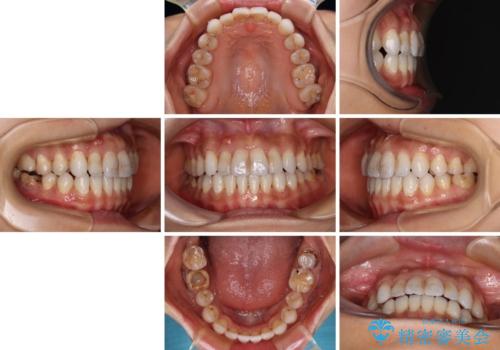

【モニター】開咬を治したい インビザラインによる矯正治療

- 上下前歯の開咬とデコボコを気にして来院された患者様です。

開咬(オープンバイト)はインビザラインによる矯正治療がワイヤー装置と比べて圧倒的に有利であるため、インビザラインによる矯正治療を行うこととしました。

通院されなかった時期があって治療期間が長くなったり、奥歯に抜歯が必要な歯があったりと、治療は一筋縄にはいきませんでしたが、何とか治療を終えることができました。

今後はインプラント治療やむし歯治療を進めて行く予定です。